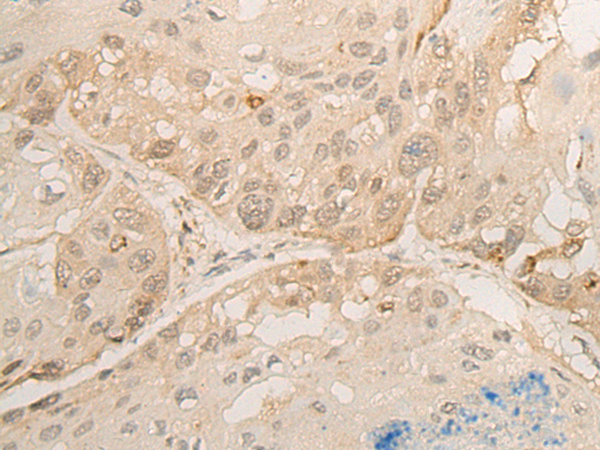

IHC positive control: |

Human esophagus cancer; |

IHC Recommend dilution: |

30-150 |